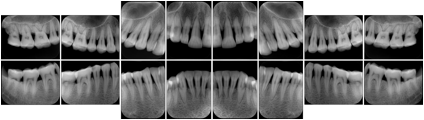

Table OO.1.1-1 shows structured display standard templates, where Viewset ID is based on the Japanese Society for Oral and Maxillofacial Radiology (JSOMR) classification provided by JIRA (Japan Medical Imaging and Radiological Systems Industries Association, www.jira-net.or.jp). Expected or typical teeth to be imaged location, region and designation codes are based on ISO 3950-2010, Dentistry - Designation system for teeth and areas of the oral cavity. For all the hanging protocols listed in OO.1.1-1, the value to use for Hanging Protocol Creator (0072,0008) is "JSOMR" and the value to use for Hanging Protocol Name (0072,0002) does not include "JSOMR" (e.g., "DL-S001A", not "JSOMR DL-S001A").